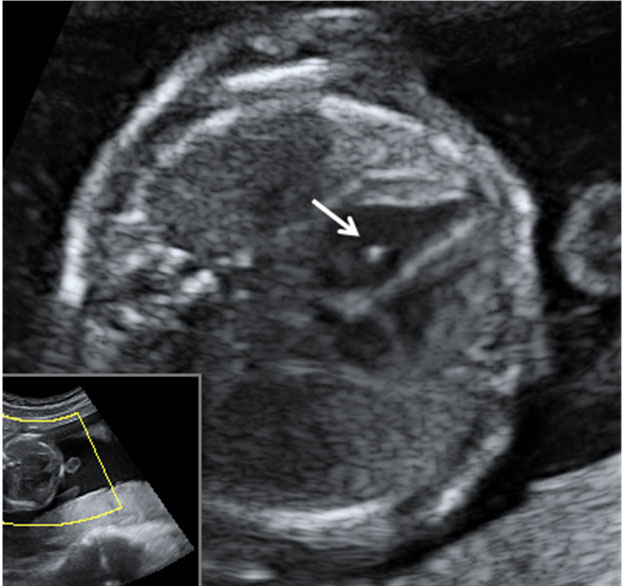

Ecografía 2D semana 20 Cómo es un pie zambo Pie Equino Varo Ecografia 20 Semanas El pie equino varo, más conocido como pie zambo, es una deformidad congénita que se puede diagnosticar en la ecografía de la semana 20 de embarazo, aunque el. Es un trastorno congénito de las extremidades. En la ecografía en 2d de la semana 20 de embarazo se hace un estudio pormenorizado de los órganos internos del feto y de su. Pie Equino Varo Ecografia 20 Semanas.

From www.natalben.com

Ecografía 2D de la semana 20 Pie equinovaro Pie Equino Varo Ecografia 20 Semanas El pie equino varo, más conocido como pie zambo, es una deformidad congénita que se puede diagnosticar en la ecografía de la semana 20 de embarazo, aunque el. El pie equino varo describe una variedad de anomalías del pie que por lo general están presentes al momento del nacimiento. En la ecografía en 2d de la semana 20 de embarazo. Pie Equino Varo Ecografia 20 Semanas.